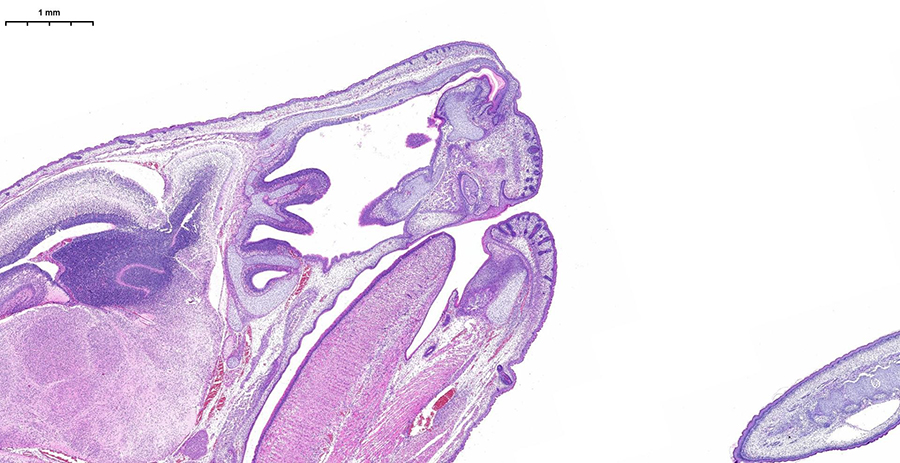

Сможете оценить высочайшее разрешение, скорость обработки (полное стекло за 3-5 минут) и интеллектуальное аналитическое ПО, которое автоматически распознаёт структуры и формирует количественные отчёты с готовыми данными. Можно принести для апробации свои образцы, демонстрируемая конфигурация флуоресцентных каналов (Ex/Em, нм):